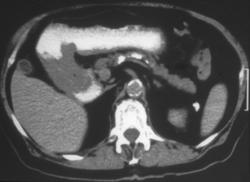

Diagnosis

H. Pylori